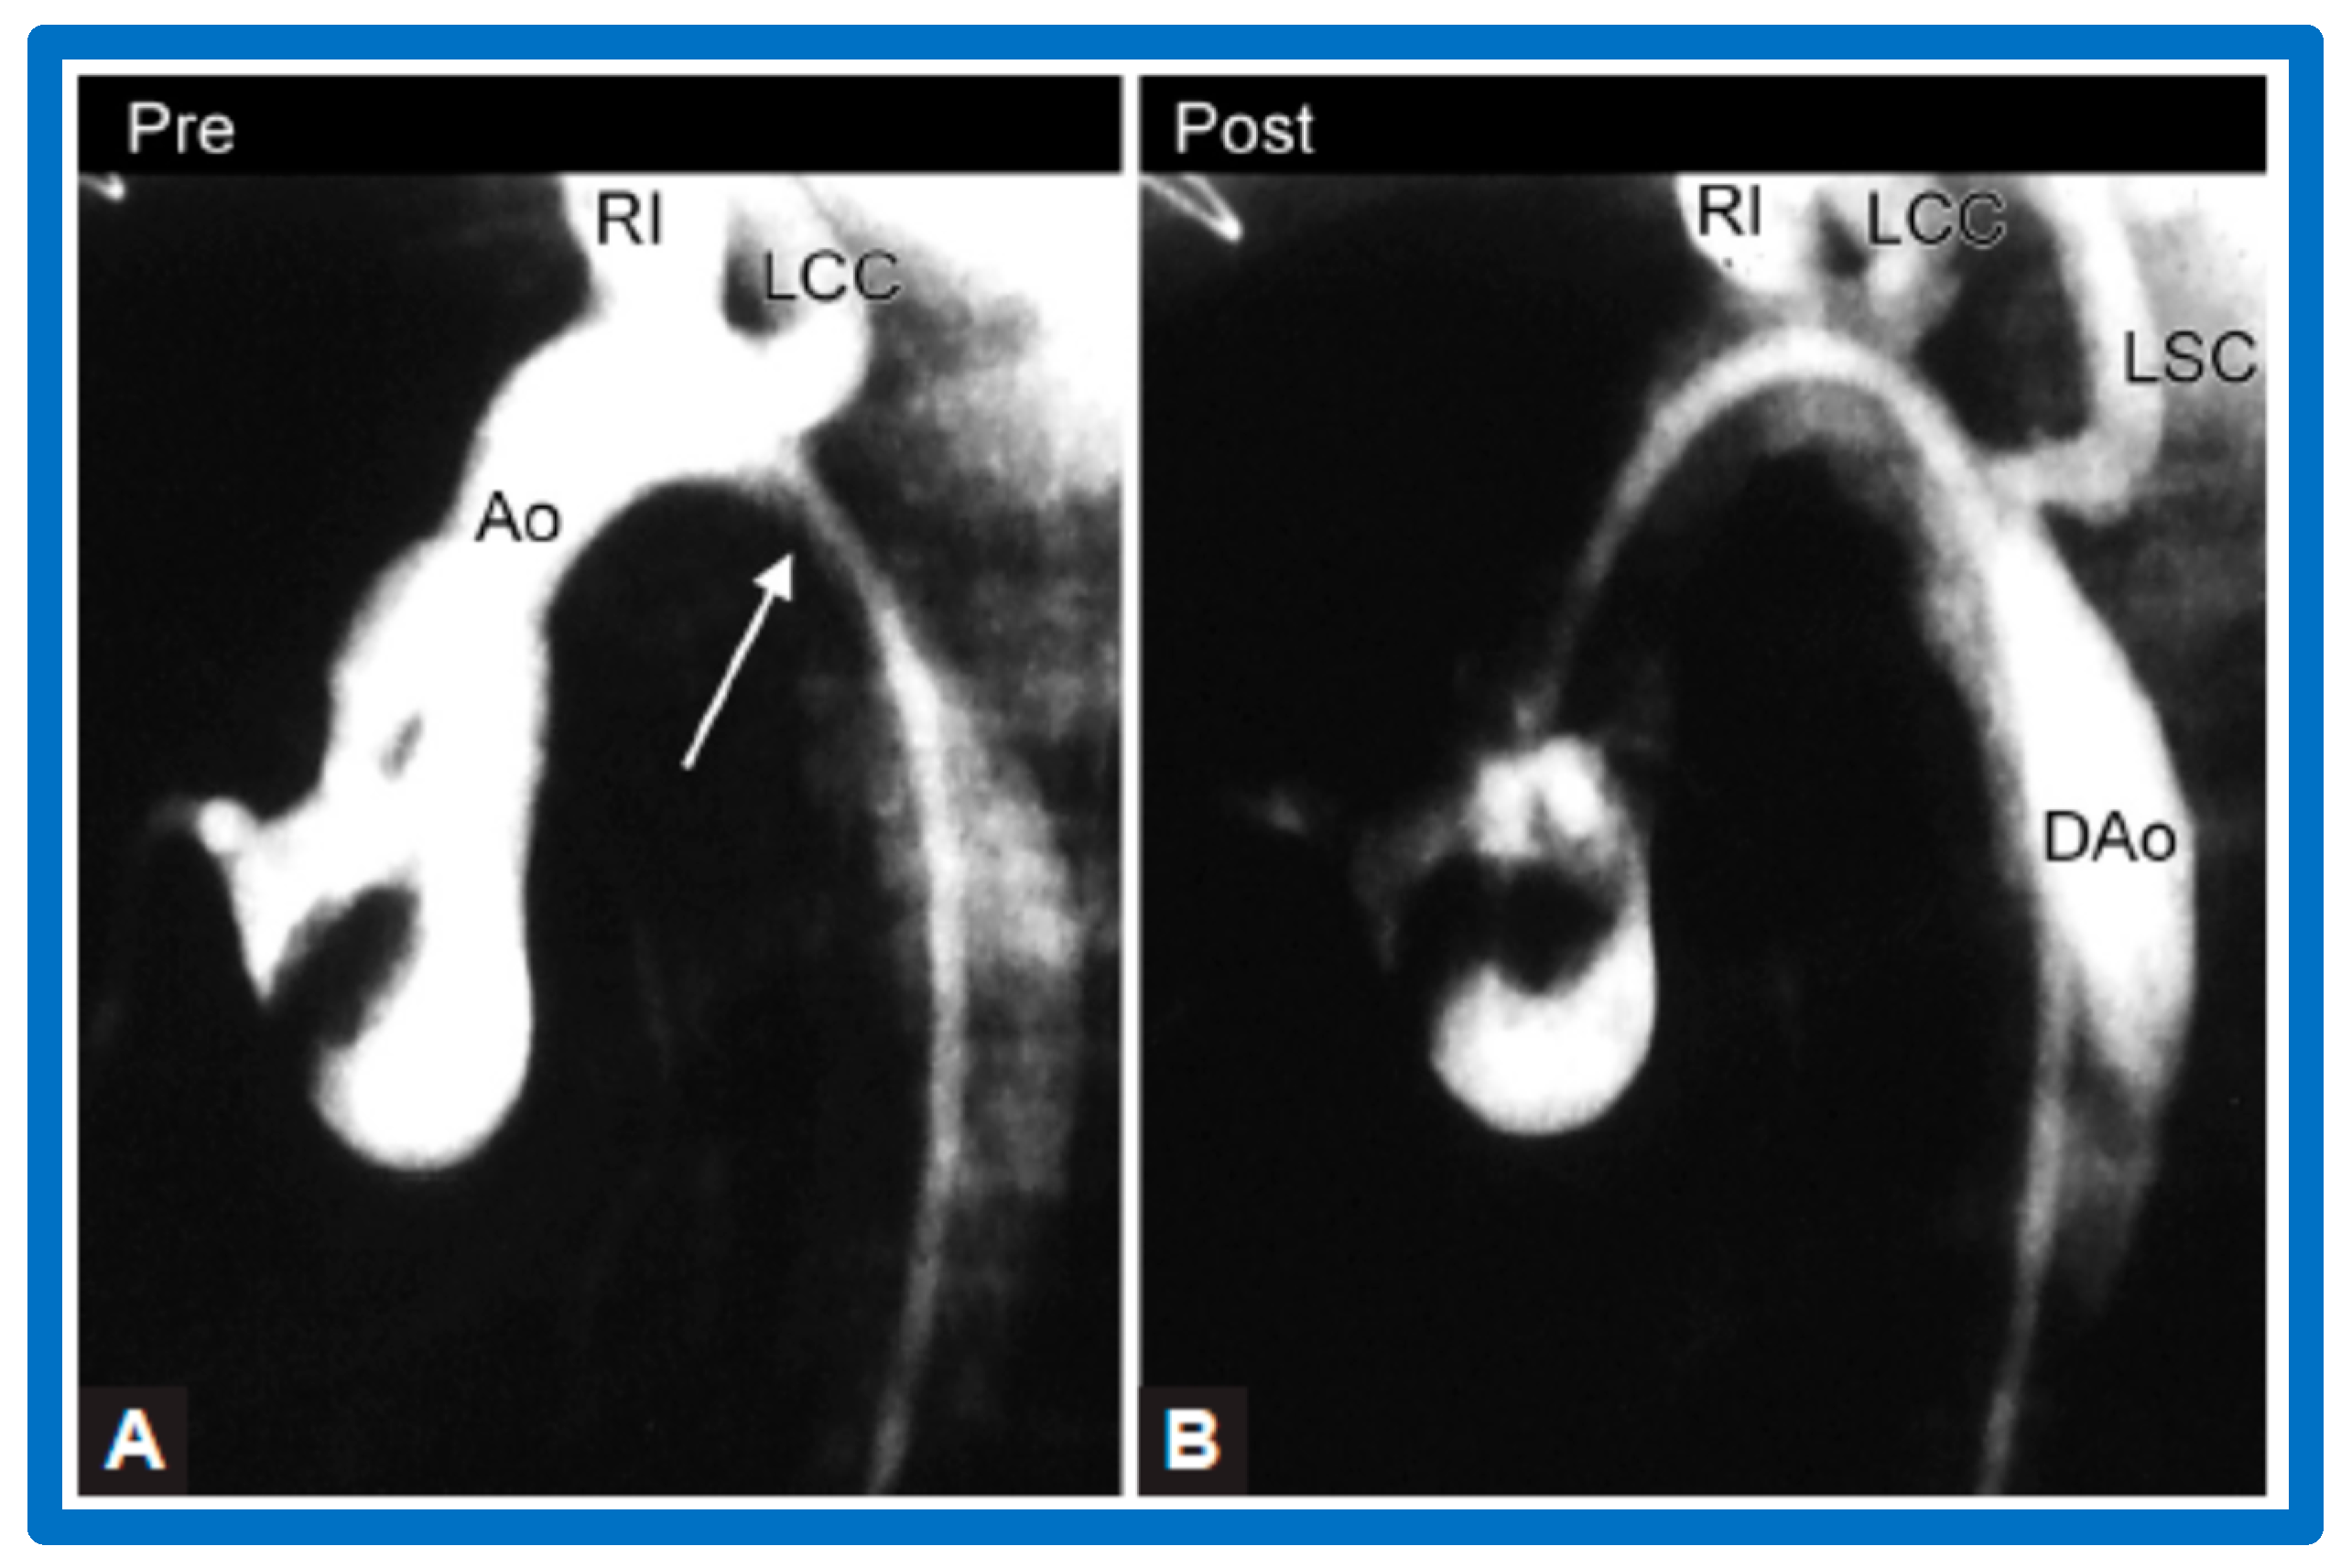

4.4. Aortic Coarctation, Postsurgical

5.4. Aortic Coarctation, Postsurgical

6. Long-Term Results